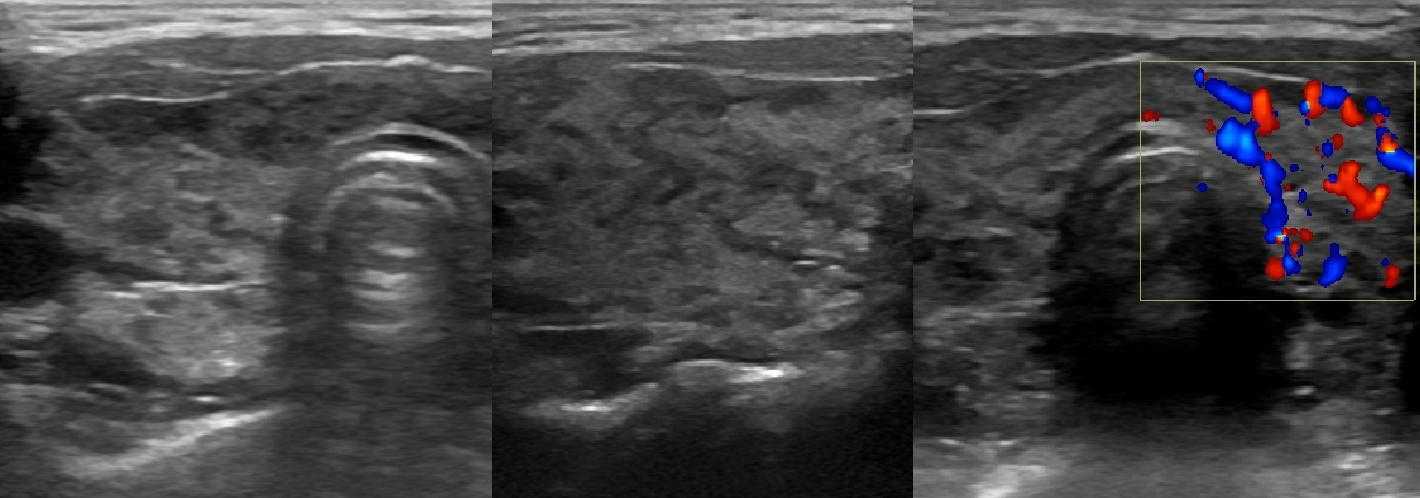

При аутоиммунном тиреоидите на УЗИ паренхима гипоэхогенная, грубонеоднородной за счет узелков (2-6 мм) разной эхогенности, неправильной формы. Очаги изоэхогенные к ткани слюнных желез пока не вовлечены в воспаление; в резко гипоэхогенных фокусах воспаление максимально выражено; в гиперэхогенных округлых или линейных структурах произошло замещение паренхимы на соединительную ткань. При тиреоидите Хашимото аномальная УЗ-картина сохраняется на протяжении всей жизни пациента. Подробнее смотри Аутоиммунная щитовидная железа на УЗИ (лекция на Диагностере).

Рисунок. Девочка 10-ти лет с эутиреозом и антитиреоидными антителами. На УЗИ щитовидная железа увеличена в 1,5 раза — 13 см3 (норма до 8,3 см3). На фоне неизмененной паренхимы определяются гипоэхогенные «змеи» (лимфоидная инфильтрация по ходу сосудов). Кровоток заметно усилен. Заключение: АИТ, гипертрофическая форма. Аналогично может начинаться диффузный токсический зоб.

Рисунок. Пациент с гипотиреозом и антитиреоидными антителами. На УЗИ щитовидная железа диффузно увеличена; контур волнистый; на фоне нормальной паренхимы в большом количестве гипоэхогенные очаги (3-5 мм) с четким контуром без «гало». Заключение: АИТ, гипертрофическая форма.

Рисунок. Пациент с гипертиреозом и антитиреоидными антителами. На УЗИ щитовидная железа диффузно увеличена; на фоне общего снижения эхогенности определяются гипоэхогенные включения (2-4 мм) и линейные гиперэхогенные структуры; кровоток заметно усилен. Заключение: АИТ, гипертрофическая форма.